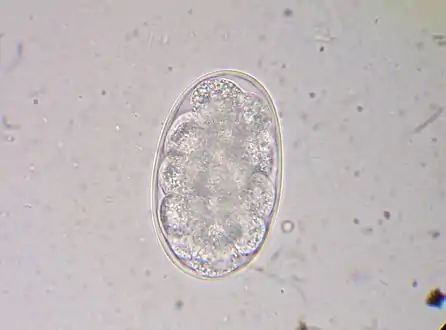

Diagnosis depends on finding characteristic worm eggs on microscopic examination of the stools, although this is not possible in early infection. Early signs of infection in most dogs include limbular limping and anal itching. The eggs are oval or elliptical, measuring 60 by 40 µm, colorless, not bile stained and with a thin transparent hyaline shell membrane. When released by the worm in the intestine, the egg contains an unsegmented ovum. During its passage down the intestine, the ovum develops and thus the eggs passed in feces have a segmented ovum, usually with 4 to 8 blastomeres. As the eggs of both Ancylostoma and Necator (and most other hookworm species) are indistinguishable, to identify the genus, they must be cultured in the lab to allow larvae to hatch out. If the fecal sample is left for a day or more under tropical conditions, the larvae will have hatched out, so eggs might no longer be evident. In such a case, it is essential to distinguish hookworms from Strongyloides larvae, as infection with the latter has more serious implications and requires different management. The larvae of the two hookworm species can also be distinguished microscopically, although this would not be done routinely, but usually for research purposes. Adult worms are rarely seen (except via endoscopy, surgery or autopsy), but if found, would allow definitive identification of the species. Classification can be performed based on the length of the buccal cavity, the space between the oral opening and the esophagus: hookworm rhabditoform larvae have long buccal cavities whereas Strongyloides rhabditoform larvae have short buccal cavities.[19][4][37]

- Hookworm egg